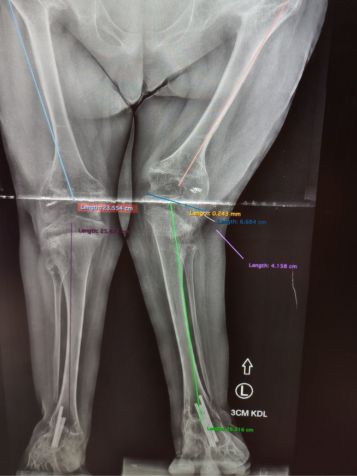

Wiadomość ta była dla nas ciosem, kolejnym, który musieliśmy przyjąć, by powstać i walczyć dalej. W ciągu roku jej noga skróciła się o 3 cm., Kasia chodzi na zwichniętych biodrach, wykrzywiona kość udowa powoduje rotację kolana do środka, dodatkowo krzywo rosnąca kość piszczelowa pogłębia rotację kolana, powoduje to ogromny ból i dyskomfort, oraz grozi utratą tego nad czym tak mocno pracowaliśmy - możliwości samodzielnego poruszania się. Konieczna jest pilna operacja osteotomii bliższej kości piszczelowej lewej nogi, w celu wyprostowania jej. Mamy już kosztorys z USA i brakuje nam 200 tys. zł - o taką kwotę zwiększamy licznik. Operacja została wyznaczona na 20 maja! Wszystko wskazuje na to, że po tej interwencji chirurgicznej konieczna będzie operacja zwichniętych bioder. Dopiero później przyjdzie czas na wydłużenie rączek, niestety dla Kasi, gdyż bardzo czekała na taką operację, w nadziei na utęsknioną samodzielność… Byliście z Kasią przez ten cały czas, nie zostawiajcie jej i teraz w tak trudnej sytuacji!